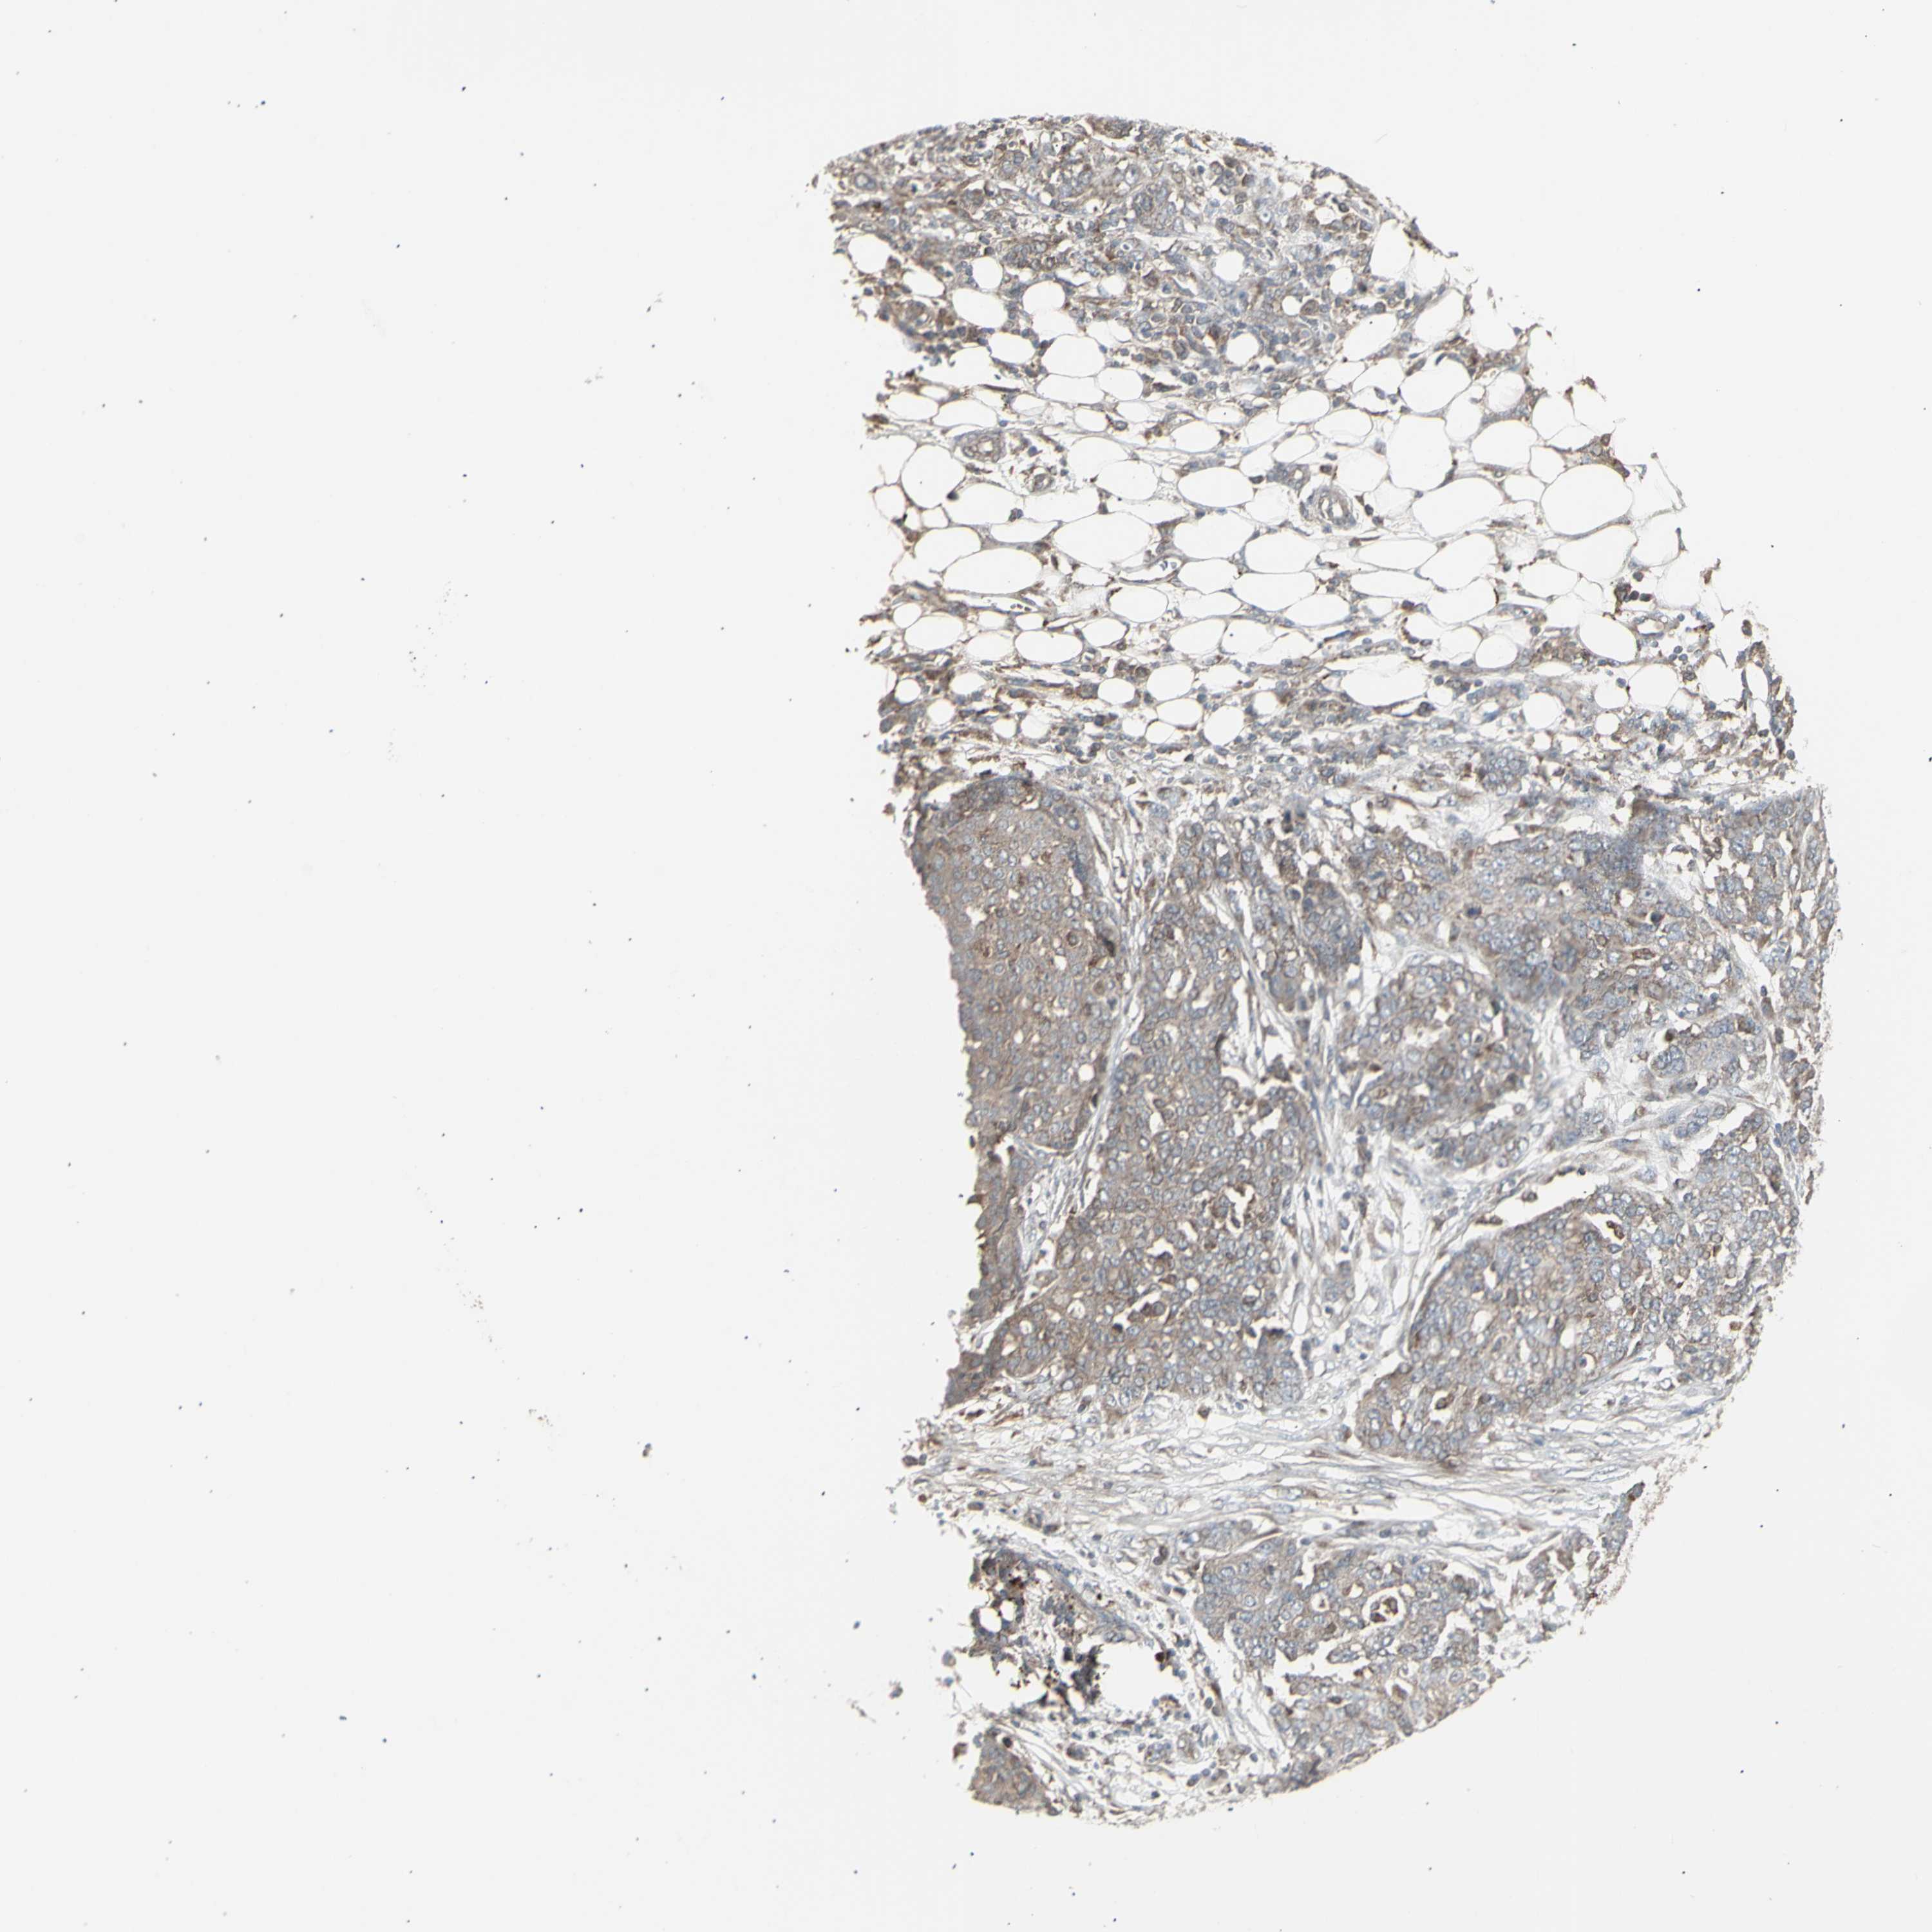

OVARIAN CANCER - Protein expressioni

A mouse-over function shows sample information and annotation data. Click on an image to view it in a full screen mode. Samples can be filtered based on level of antibody staining by selecting one or several of the following categories: high, medium, low and not detected. The assay and annotation is described here.

Note that samples used for immunohistochemistry by the Human Protein Atlas do not correspond to samples in the TCGA dataset.

Antibody stainingi

Antibody staining in the annotated cell types in the current human tissue is reported as not detected, low, medium, or high, based on conventional immunohistochemistry profiling in selected tissues. This score is based on the combination of the staining intensity and fraction of stained cells.

Each image is clickable and will lead to virtual microscopy that enables deeper exploration of all samples and also displays staining intensity scores, fraction scores and subcellular localization as well as patient and tissue information for each sample.

Antibody HPA002633

Antibody HPA046758

Antibody CAB010906

Carcinoma, endometroid

Cystadenocarcinoma, serous, NOS

Cystadenocarcinoma, mucinous, NOS

Carcinoma, NOS